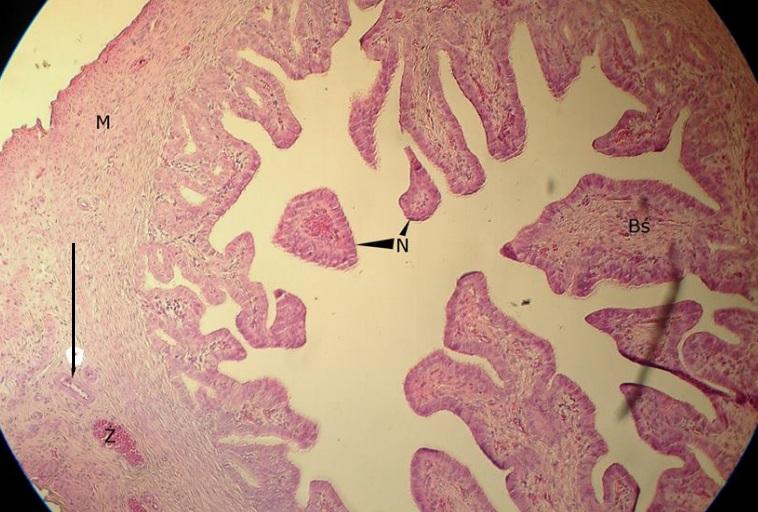

Pytanie 670

tętnica (jajowód)

Pytanie 671

Pytanie 672

żyła (jajowód)